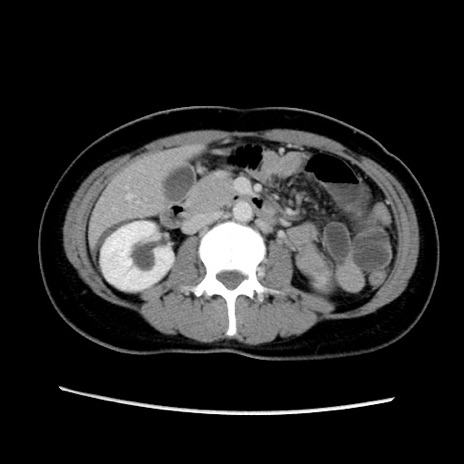

症例39(横断像)

【症例】40歳代女性

【主訴】上下腹部痛

【現病歴】2日目から下腹部痛あり。夜間は痛みで眠れなかった。昨日より上腹部痛と下痢が出現。臥位で痛みは軽快したため、休んでいた。本日になって臥位でも立位でも痛みが強くなってきたため救急要請。

【既往歴】子宮内膜症

【身体所見】部:平坦・軟、左上下腹部に圧痛あり、反跳痛あり。

【データ】WBC 21800、CRP 26.78